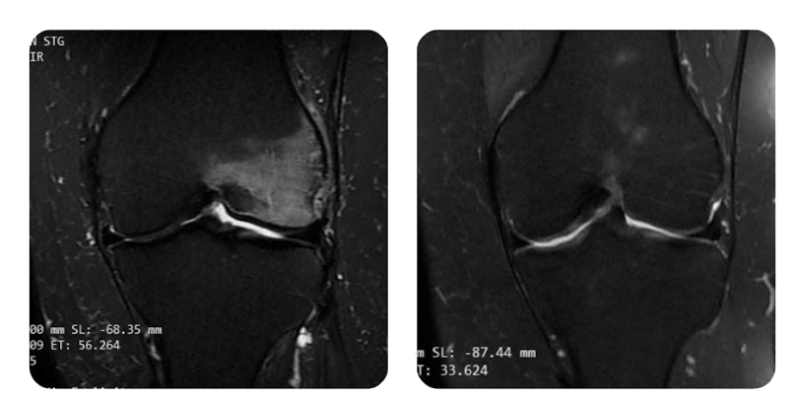

Prima

Dopo

G.O., 54 anni - Necrosi del condilo femorale esterno sinistro

Anamnesi: Paziente di 54 anni con dolore al ginocchio; dopo RMN è stata posta diagnosi di necrosi del condilo femorale esterno sinistro.

Diagnosi: Necrosi del condilo femorale esterno sinistro.

Evoluzione: Al controllo dopo il primo ciclo (20 sedute), il paziente ha riportato riduzione dell'intensità del dolore del 60%. La RMN ha evidenziato riduzione dell'edema dell'80%.

Dopo il secondo ciclo (40 sedute totali), al nuovo controllo il dolore si è ridotto da 10/10 a 2/10. Radiologicamente, l'edema si è ridotto del 95%.